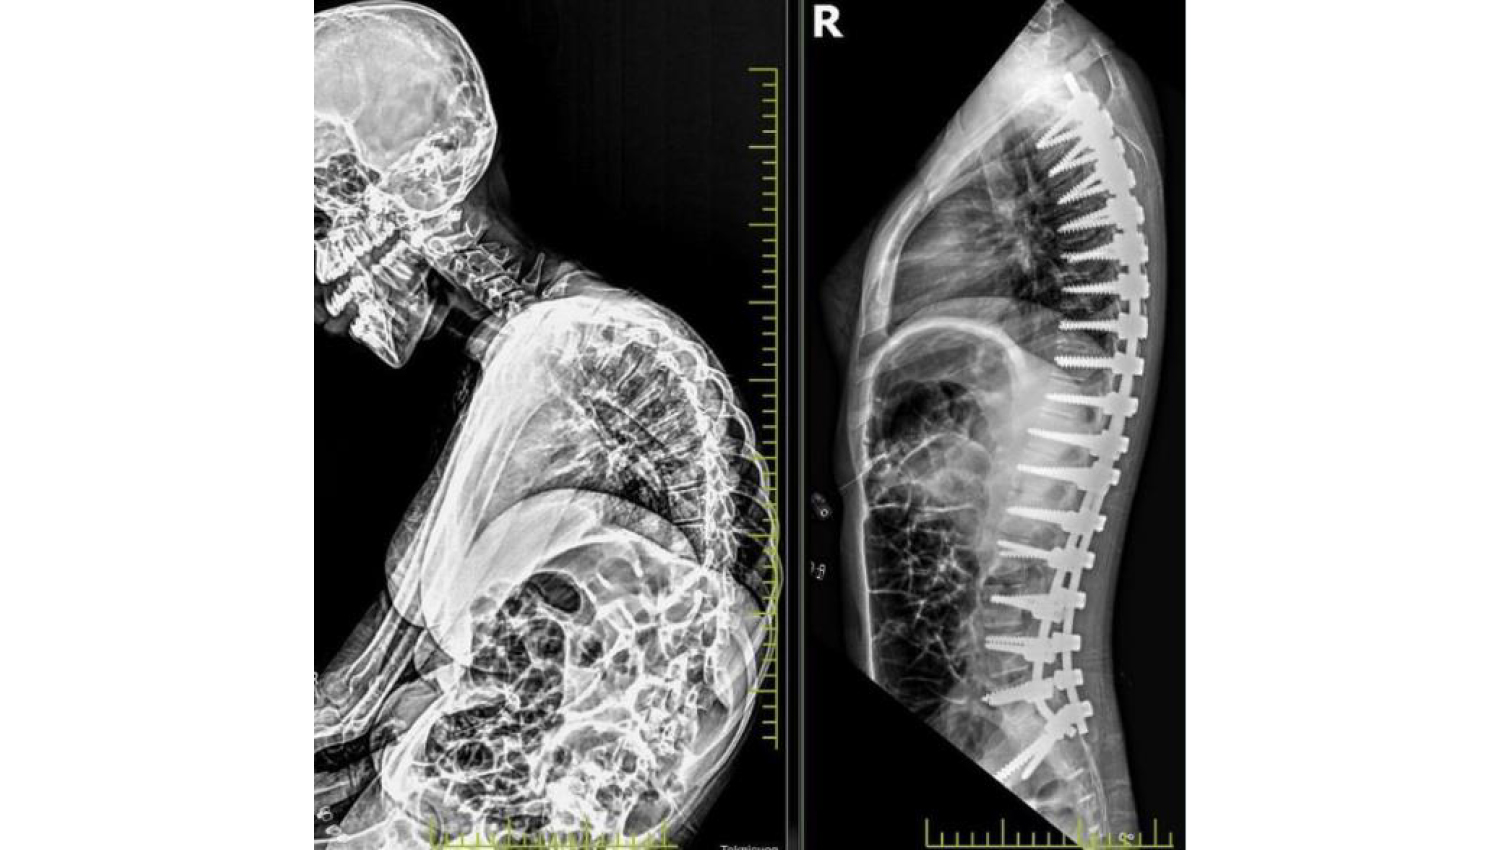

3.Post-operation radiological view.

4.Before and after radiological view.